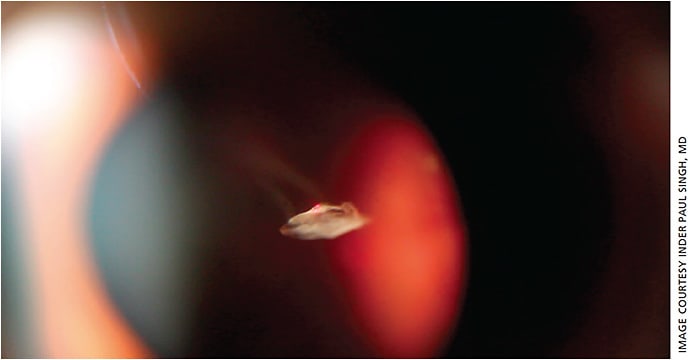

At ASCRS 2017, we also presented our data of LFT patinets with at least 1 to 4 years of follow-up. This retrospective study included 1272 procedures performed in 680 patients.8 Patients with both amorphous and solitary Weiss ring type of floaters were included. Ten adverse events were recorded (0.8%), comprising seven cases of IOP spikes, two cases of hitting the phakic lens (Figure 10) and one retinal hemorrhage (this included the adverse events fromt the 130 cases in the 2016 prospective paper). Patients with IOP spikes were placed on topical antihypertensive medications (average post-medication IOP, 19 mm Hg). The one of the phakic patients subsequently required cataract surgery and achieved a corrected visual acuity of 20/20, while the other patient is still being observed. The case of retinal hemorrhage resolved in 3 months with no long-term negative effects. There were no inflammatory issues faced, no AC or Vitreous cell or flare seen., nor was there exacerbation of diabetic retinopathy, progression of ERM or cystoid macular edema. Postoperative regimen for all cases included IOP checks immediately after the procedure, at 1 week, and 1 month. No anti-inflammatory drops or topical antihypertensive meds were given.